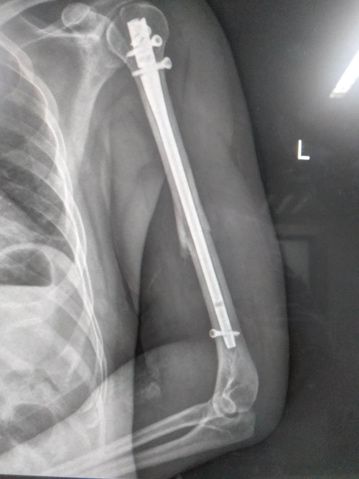

术后X片

完善相关术前检查,无手术禁忌,徐勇强主治医师带领手术团队为患者实施急诊微创手术,只留下3个约2cm的微创切口,患者术后第一天便开始行功能锻炼。